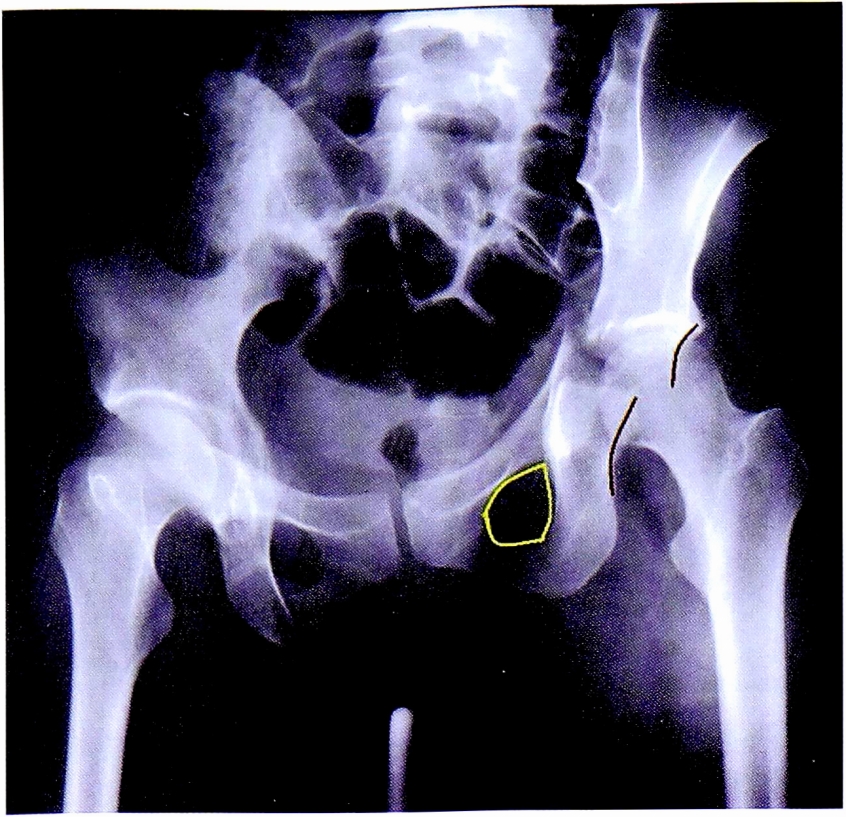

На рис. 12 представлена обзорная рентгенограмма таза. По данному снимку возможно заподозрить перелом левой вертлужной впадины, поскольку определяется незначительная деформация подвздошногребешковой линии с нарушением ее непрерывности.

Рис. 12. Обзорная рентгенография таза пациента с подозрением на перелом вертлужной впадины.

Fig. 12. АР Pelvic X-ray of patient with suspected acetabular fracture.

После выполнения прицельной рентгенографии в косой подвздошной проекции по методике НМИЦ TO, выявлена линия перелома, проходящая через крыло подвздошной кости, сурсил и нижние отделы передней колонны. Также на прицельной рентгенограмме отчетливо видна интактность задних отделов вертлужной впадины (рис. 13).

Рис. 13. Рентгенография левого тазобедренного сустава в косой-подвздошной проекции, выполнена по методике НМИЦ ТО. Стрелками показана линия перелома в местах прохождения через визуализируемые структуры вертлужной впадины.

Fig. 13. Iliac oblique view made CITO method. Arrows shows fracture lines crossing acetabulum.